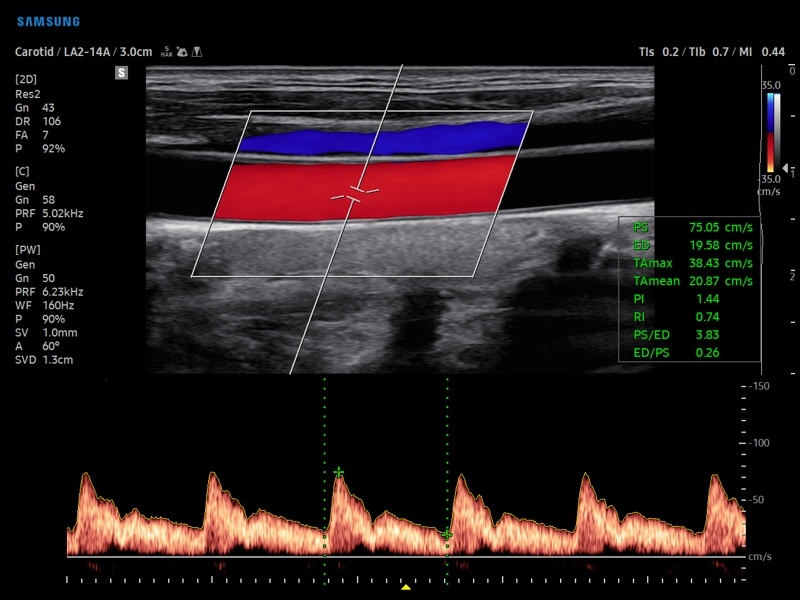

• PW - импульсно-волновой допплер, steering - изменение допплеровского угла в режимах CD и PD, автоматический анализ допплеровских кривых.

• Модуль AutoIMT - автоматическое вычисление комплекса интима-медиа общей сонной артерии (Intima Media Thickness). Данная оценка имеет большое значение для ранней диагностики атеросклероза и оценки риска развития инсульта и инфаркта миокарда.

• Модуль 2D Arterial Analysis программа, позволяющая автоматически провести анализ толщины и эластичности стенок разных участков сонной артерии, с выведением результатов в графической форме в движении (кинопетле) аналогично программе Strain для эхокардиографии.

• Сонные артерии:автоматическая, полуавтоматическая, ручная трассировка доплеровского спектра; ПСС, КДС, %СтПлощ, %Ст Диам, площадь сосуда, диаметр сосуда, средняя толщина интимы, объемный кровоток.